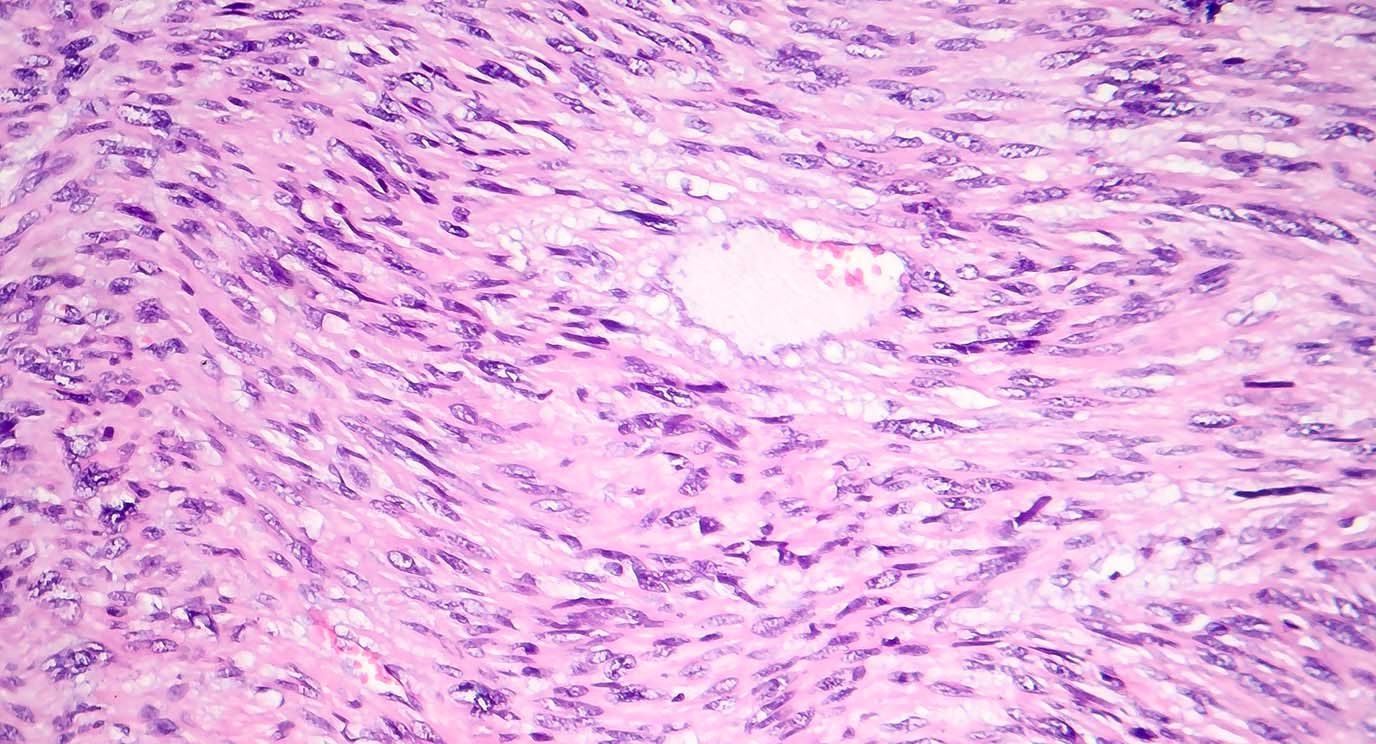

The Sarcoma and Orthopaedic Center treats more than 100 different cancers and tumors of the bones and soft tissue, including muscle, joint tissue and blood vessels. These tumors can arise all over the body, including in the arms, legs, trunk and abdomen.

Sarcomas overall are rare and complex. Some are extremely rare, with only a few dozen cases diagnosed each year.

- All soft tissue sarcomas, including leiomyosarcoma, liposarcoma and undifferentiated pleomorphic sarcoma

- All bone sarcomas, including osteosarcoma, Ewing’s sarcoma, chondrosarcomas and chordoma